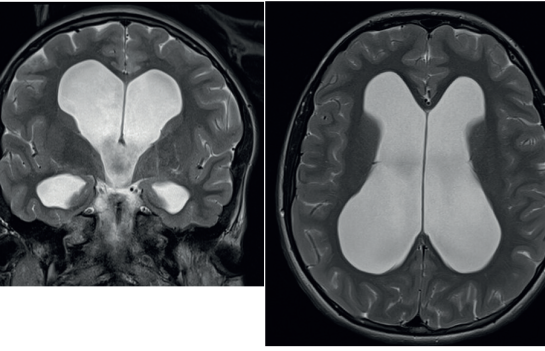

V naší kazuistice hraje ústřední roli patnáctiletá dívka, která byla sledována dětskou neuroložkou pro měsíce trvající silné bolesti hlavy. Tyto byly lokalizovány do oboustranných spánkových oblastí bez návaznosti na specifické činnosti, polohu či jiné faktory. Bolesti byly přítomny denně, dívka často vynechávala ve škole, kde se i beztak její prospěch horšil kvůli poruše pozornosti a paměti. Ošetřující neuroložka indikovala magnetickou rezonanci (MR) mozku, kde byla nalezena dilatace komorového systému (obr. 1). S tímto byla pacientka přijata do naší péče. V anamnéze nebyly vystopovány žádné rizikové faktory pro vznik hydrocefalu – perinatální anamnéza byla negativní, pacientka neprodělala žádný neuroinfekt či úraz hlavy. Na MR mozku byla viditelná výrazná dilatace komorového systému, zejména supratentoriálně, nicméně ani IV. komora nebyla fyziologické šíře. Dále bylo nápadné zúžení vtokové části aquaeductus mesencephali s velmi výrazným tokovým artefaktem na PSIF, tedy sekvenci určené k detekci toku likvoru (obr. 2), obraz zúžení mokovodu s hyperdynamickým tokem likvoru. To podporoval i výrazný bowing III. komory, tedy vyboulení III. komory a vyhlazování jejích výklenků, turecké sedlo však nebylo zvětšeno ani nikterak destruováno (obr. 3). Po příjmu pacientky byla provedena optická koherentní tomografie (OCT) zrakového nervu, která edém terče zrakového nervu neprokázala. Vzhledem k tomu, že se nejednalo o jasný obstrukční hydrocefalus, byla následně provedena lumbální punkce ke změření tlaku likvoru a odběru jeho vzorku k laboratorní analýze. Tlak byl v normě – 17 cm H20, v laboratorních vyšetřeních odchylka též nebyla nalezena. To znamená, že na MR mozku jsou jasné známky hydrocefalu, ale jak nález na očním pozadí, tak i lumbální punkce ukazují na normální tlak mozkomíšního moku. Vzhledem ke zmíněnému výraznému tokovému artefaktu likvoru přes aquaeductus mesencephali jsme se zaměřili na tento fenomén. Provedli jsme MR mozku metodou fázového kontrastu (Phase‑Contrast MRI, PC‑MRI), která umožňuje tokové parametry likvoru kvantifikovat. Opravdu se potvrdilo, že tok likvoru je hyperdynamický, maximální systolická rychlost byla 11,7 cm/s (obr. 4). Byla tedy vyslovena hypotéza, že se jedná o stenózu mokovodu a pacientce, a vzhledem k věku samozřejmě i rodině, byla navržena endoskopická stomie III. komory (ETV). Vzhledem k absenci mechanické obstrukce mokovodu při současně vysokých systolických rychlostech průtoku likvoru přes mokovod byla vyslovena hypotéza, že se jedná o funkční stenózu mokovodu. S přihlédnutím k věku pacientky byly ona i její rodina seznámeny s možností miniinvazivního výkonu ve smyslu endoskopické stomie III. komory (ETV). Rodina byla však k operaci rezervovaná, proto jsme nabídli tehdy novou diagnostickou metodu – miniinvazivní přímé měření intrakraniálního tlaku (ICP) čidlem s telemetrickým přenosem naměřených hodnot (Raumedic Neurovent‑P‑telâ). Hlavní výhodou této metody je možnost kontinuálního měření ICP i v domácím prostředí až po dobu 90 dnů. Implantace čidla byla provedena bez komplikace a pacientka byla edukována o způsobu monitorace ICP, zejména vedení deníku činností a bolestí hlavy. Po třítýdenním měření byla data analyzována a porovnána s deníkem. Byl nalezen jasný korelát mezi silnou cefaleou a hroty ICP až k hodnotám 30 mm Hg. Zvláště nápadné byly křivky během noci, kdy krátce po elevaci ICP byla pacientka bolestmi hlavy opakovaně vzbuzena. Po předložení výsledků této metody pacientka i rodina souhlasily s provedením ETV. Zákrok byl proveden bez komplikace, průchodnost stomie byla verifikována pooperačním vyšetřením pomocí MR mozku (obr. 5). Pooperačně se však symptomy pouze zmírnily a po pěti týdnech nastala kompletní recidiva obtíží. Byla vyslovena suspekce na okluzi stomie, nicméně kontrolní MR mozku toto nepotvrdila. Další postup mohl mít dva scénáře. První by znamenal připustit, že pacientčiny nespecifické symptomy nebyly dány porušenou likvorodynamikou a naše rozvaha byla chybná. Druhý by znamenal setrvání v našem předpokladu, že obtíže jsou spojeny s likvorodynamickými poměry, nicméně ETV nepostačovala k odvedení dostatečného objemu likvoru při jeho pulzatilním toku. Jedinou další léčebnou metodou by v tom případě bylo zavedení ventrikuloperitoneálního (VP) shuntu. Což je však další invazivní výkon, proto jsme uvažovali o další diagnostické metodě – lumbální drenáži. Jedná se ve své podstatě o simulaci zavedeného shuntu dočasnou drenáží likvoru ze spinálního subarachnoidálního prostoru. Po domluvě s pacientkou a rodinou byla lumbální drenáž zavedena a ponechána tři dny s celkovým objemem odvedeného likvoru 500 ml. Po celou dobu drenáže byla pacientka zcela bez bolestí hlavy. Test byl tedy pozitivní. Po vytažení drenáže se bolesti vrátily do dvou dnů. Nyní jsme s větší jistotou mohli indikovat zavedení VP shuntu. Protože jsme předpokládali, že nastavení ventilu shuntu nebude u takto komplexního typu hydrocefalu jednoduché, zavedli jsme typ ventilu, který umožní regulaci tlaku separátně pro horizontální a vertikální polohu těla – Miethke proGAVâ 2.0 s iniciálním nastavením 10 cm H2O a m.Blueâ s nastavením 25 cm H2O (obr. 6). Operace proběhla bez komplikace a pacientka byla propuštěna do domácího ošetřování s tím, že případné změny nastavení ventilu budou provedeny v rámci ambulantních kontrol. Při první kontrole pacientka udávala přetrvávající bolesti hlavy, proto bylo nastavení ventilu proGAVâ 2.0 pro horizontální polohu sníženo na 5 cm H2O. Při další kontrole za dva týdny pacientka popisovala kompletní vymizení původních příznaků vleže. Popisovala však symptomy předrénování, tedy výraznou cefaleu při vertikalizaci s rychlou úlevou v horizontální poloze. Proto bylo nastavení antigravitační jednotky m.Blueâ postupně zvýšeno až na maximum, tedy 40 cm H2O. Na tomto nastavení byla nalezena rovnováha mezi potřebou nízkoodporové drenáže likvoru vleže a zamezení předrénování sifonovým mechanismem vstoje. Pacientka je nyní sledována po operaci jeden rok, je zcela bez bolestí hlavy.